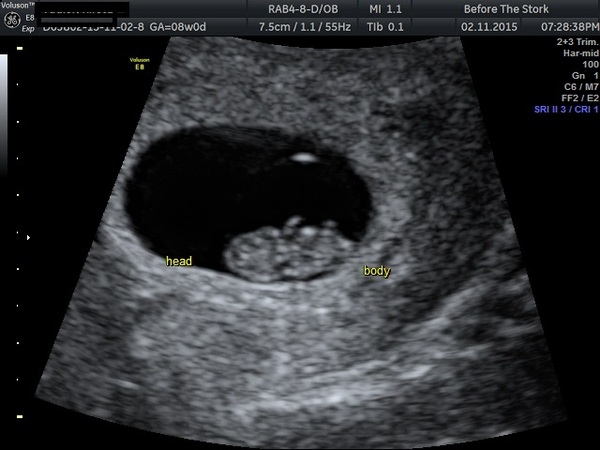

Had my scan last night and little one is fine, in the right place and has a nice strong heartbeat!! The sonographer said I looked terrified when I walked in, but I was sure she was going to tell me something was wrong, so it was such a relief. I've also moved forward a day too, I thought I was 8+0 but she said 8+1, so I'm 8+2 today. EDD 12th of June.

For people wondering about reassurance scans this one was £45 and that includes either a DVD of photos and video clips of baby or two printed out photos. That's in Liverpool by the way.